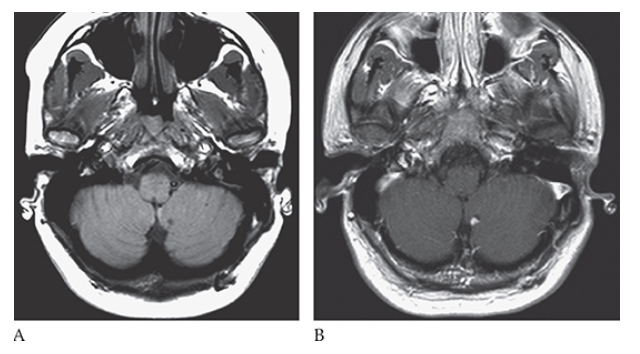

What is A

Dandy-Walker Syndrome. Axial T2W and coronal T1W

What is B

Dandy-Walker Syndrome. Axial T2W show absence of the cerebellar vermis.